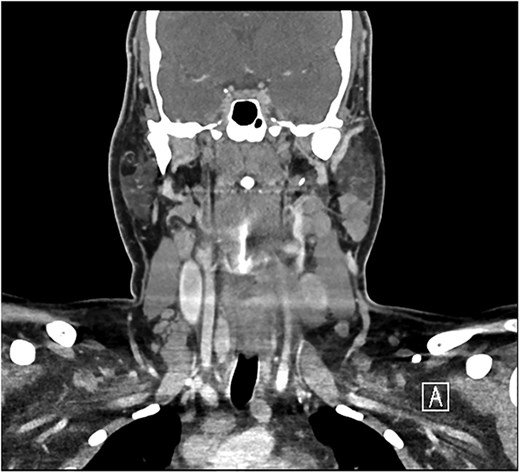

A 28-year-old man with a BMI of 44.3 kg/m2 and, a history of hypertriglyceridemia on gemfibrozil 600 mg complained of neck swelling for 2 years. It began as a nodular swelling at the right supraclavicular region and later spread to the right axillary and left supraclavicular areas. For one month, the patient had an unintentional weight loss of 4 kg and a few episodes of night sweats but no fatigue, fever, or compressive symptoms. He never received any radiation treatment. The family history was positive for an aunt with a malignant thyroid disease, for which she had a total thyroidectomy done. He was also on calcium carbonate 1200 mg orally thrice daily and levothyroxine 200 mcg orally once daily. On general examination, the patient did not look dehydrated, the patient was afebrile and did not appear to be in acute respiratory distress. There was a firm, nontender, nonmobile mass in the right anterior neck which represents lower cervical lymphadenopathy. No thyroid nodules, thrills, or shift of the trachea to the right were found. Abdominal examination was normal, that is, no enlargement or tender masses were felt on abdominal palpation. It started in January 2018 with right sided lymph node enlargement and a detailed assessment was done at a hospital in the United Kingdom (UK) in March 2020. FNA of the neck nodes showed features of HL and the thyroid US showed a hypoechoic nodule with punctate calcifications measuring 3.9 × 1.9 cm and TI-RADS 5. Other findings were bilateral clinically suspicious cervical lymphadenopathy; the largest nodes being 3.6 × 2 cm on the right side and 2.8 × 1.3 cm on the left side. The laboratory findings included T3 of 5.19 pmol/L, T4 of 25 pmol/L, and thyroid stimulating hormone (TSH) of 0.817μIU/ml. According to these observations, the patient underwent further investigations and imaging, CT of the chest revealed necrotic mediastinal, bilateral axillary, and subpectoral lymph nodes suggesting intrathoracic metastases most probably from PTC or lymphoma (Fig. 1). A nuclear medicine scan confirmed FDG-avid disease in the thyroid and nodal areas above the diaphragm. A subsequent FNA of the thyroid nodule revealed papillary thyroid carcinoma (Fig. 2). The patient had a total thyroidectomy, central compartment lymph node dissection, and excision in March 2020. Surgical pathology showed PTC in the right thyroid lobe measuring 2.5 cm in diameter and ipsilateral cervical lymph node involvement. The postoperative treatment included radioactive iodine ablation of 120 mCi in December 2020, and thyroglobulin level was negative. However, the patient got other symptoms by November 2023 after the above-mentioned interventions were conducted. Postoperative US of the neck, done after thyroidectomy, did not demonstrate any thyroid tissue but multiple enlarged cervical lymph nodes, including one that was 2.3 × 1.2 cm in size, with some of the nodes matted and non-encapsulated with loss of fatty hilum. CT imaging revealed an interval increase in the size of right cervical and supraclavicular LN (Fig. 3) and nuclear imaging showed relapsed HL with FDG-avid lymph nodes, above and below the diaphragm. The histopathological examination of the right cervical lymph node excisional biopsy was done and immunohistochemistry staining of markers compatible with CHL was observed (Figs 4 and 5). The tumor cells were positive for CD 30, CD 15 (partially), MUM 1, and PAX 5 (faintly), and the reactive lymphocytes for CD 3 only. The diagnosis of relapse of classical Hodgkin lymphoma (CHL) called for additional oncologic assessment and intervention.

Bilateral enlarged and necrotic left intraparotid, cervical, and supraclavicular lymph nodes.